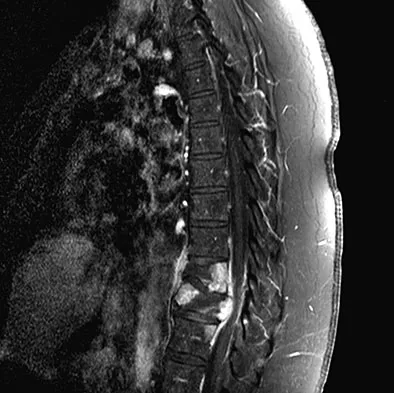

A 42-year-old man with a history of renal cell carcinoma has progressive weakness in the lower extremities for the past 3 weeks. The patient desires intervention. A sagittal T2-weighted MRI scan is shown in Figure 9a, and a sagittal contrast enhanced T1-weighted MRI scan is shown in Figure 9b. He currently ambulates minimal distances with a walker. His life expectancy is 8 months. Treatment of the spine lesion should consist of

Detailed Explanation